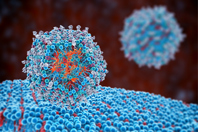

Cell therapy’s future depends on smarter gene delivery. Learn how lipid nanoparticles offer a scalable, cell-friendly alternative to electroporation and viral vectors for manufacturing efficiency.